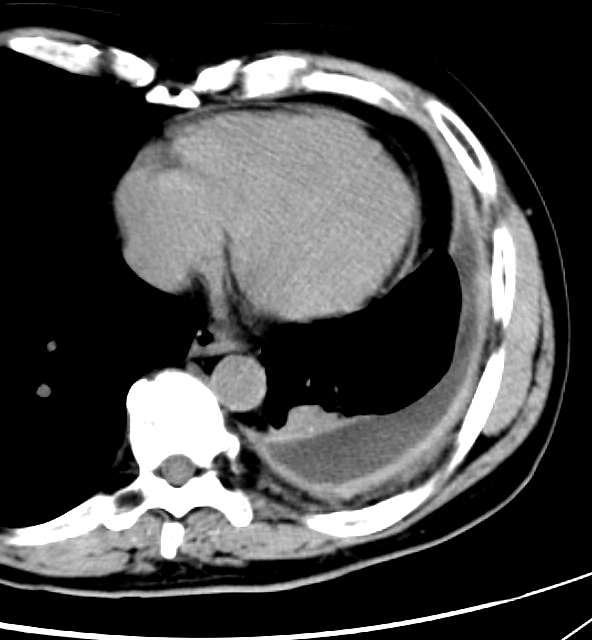

Gallery Pleural empyema split pleura

empyema split pleura